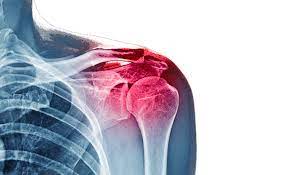

1. Don’t Miss These Pathologies of the Shoulder Joint – Part 2 By Dr. Gursimran Singh Anand

1️⃣ Covers important shoulder joint pathologies and their clinical significance.

2️⃣ Focus on disorders, features, and management explained conceptually.

3️⃣ High-yield session for MBBS, NEET PG, DNB, and INI SS preparation.

4️⃣Ideal for mastering musculoskeletal imaging in an exam-oriented way.